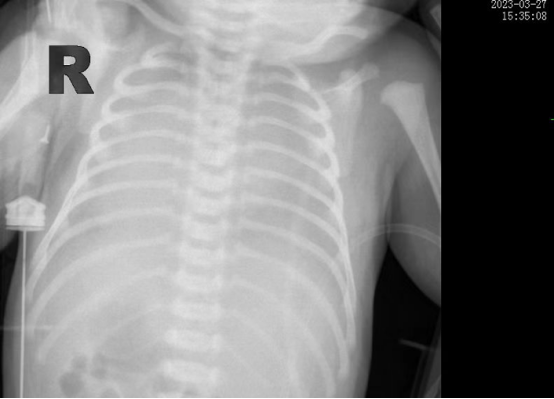

時間追溯到3月27日,該患兒出生時哭聲欠連貫,全身可見黃色胎糞附著,羊水三度污染,呼吸稍促,血氧飽和度低,立即轉(zhuǎn)入新生兒科。醫(yī)生立即予以清理呼吸道,常壓給氧,建立靜脈通道后抱入暖箱復溫,同時以無創(chuàng)輔助通氣。然而患兒呼吸窘迫癥狀正在進行性加重,胸片提示“白肺”,結合血氣分析等檢查后,患兒被診斷為“急性呼吸窘迫綜合癥”、“呼吸衰竭”。時間就是生命,主管醫(yī)生張海嬌在與家屬充分溝通同時,副主任醫(yī)師鐘玉芬立即帶領新生兒醫(yī)護團隊快速采取急救措施,給予患兒氣管插管術進行有創(chuàng)呼吸機高頻震蕩通氣,并從氣管內(nèi)滴入PS(肺表面活性物質(zhì)),以降低肺泡表面張力,增加肺順應性,患兒血氧這才穩(wěn)定下來。

在科室團隊的共同努力下,患兒歷經(jīng)5天有創(chuàng)通氣5天無創(chuàng)通氣,再調(diào)整為5天吸氧后已經(jīng)實現(xiàn)呼吸自由,復查肺部CT,終于看到白肺已云開霧散。4月15日,歷時17天的醫(yī)療救治,患兒順利出院,回到了媽媽的懷抱。

據(jù)悉,新生兒急性呼吸窘迫綜合征(ARDS)是一種嚴重威脅新生兒生命的呼吸危重癥,其主要臨床表現(xiàn)為不同程度的低氧血癥,雙肺彌漫性透光度下降,炎性滲出伴肺順應性下降。根據(jù)國際新生兒ARDS多中心研究中期報告,新生兒ARDS病死率大約為20%,而早期識別,進行良好的肺復張,預防及治療肺動脈高壓、心臟衰竭、液體管理及積極抗感染等綜合治療以降低病死率。